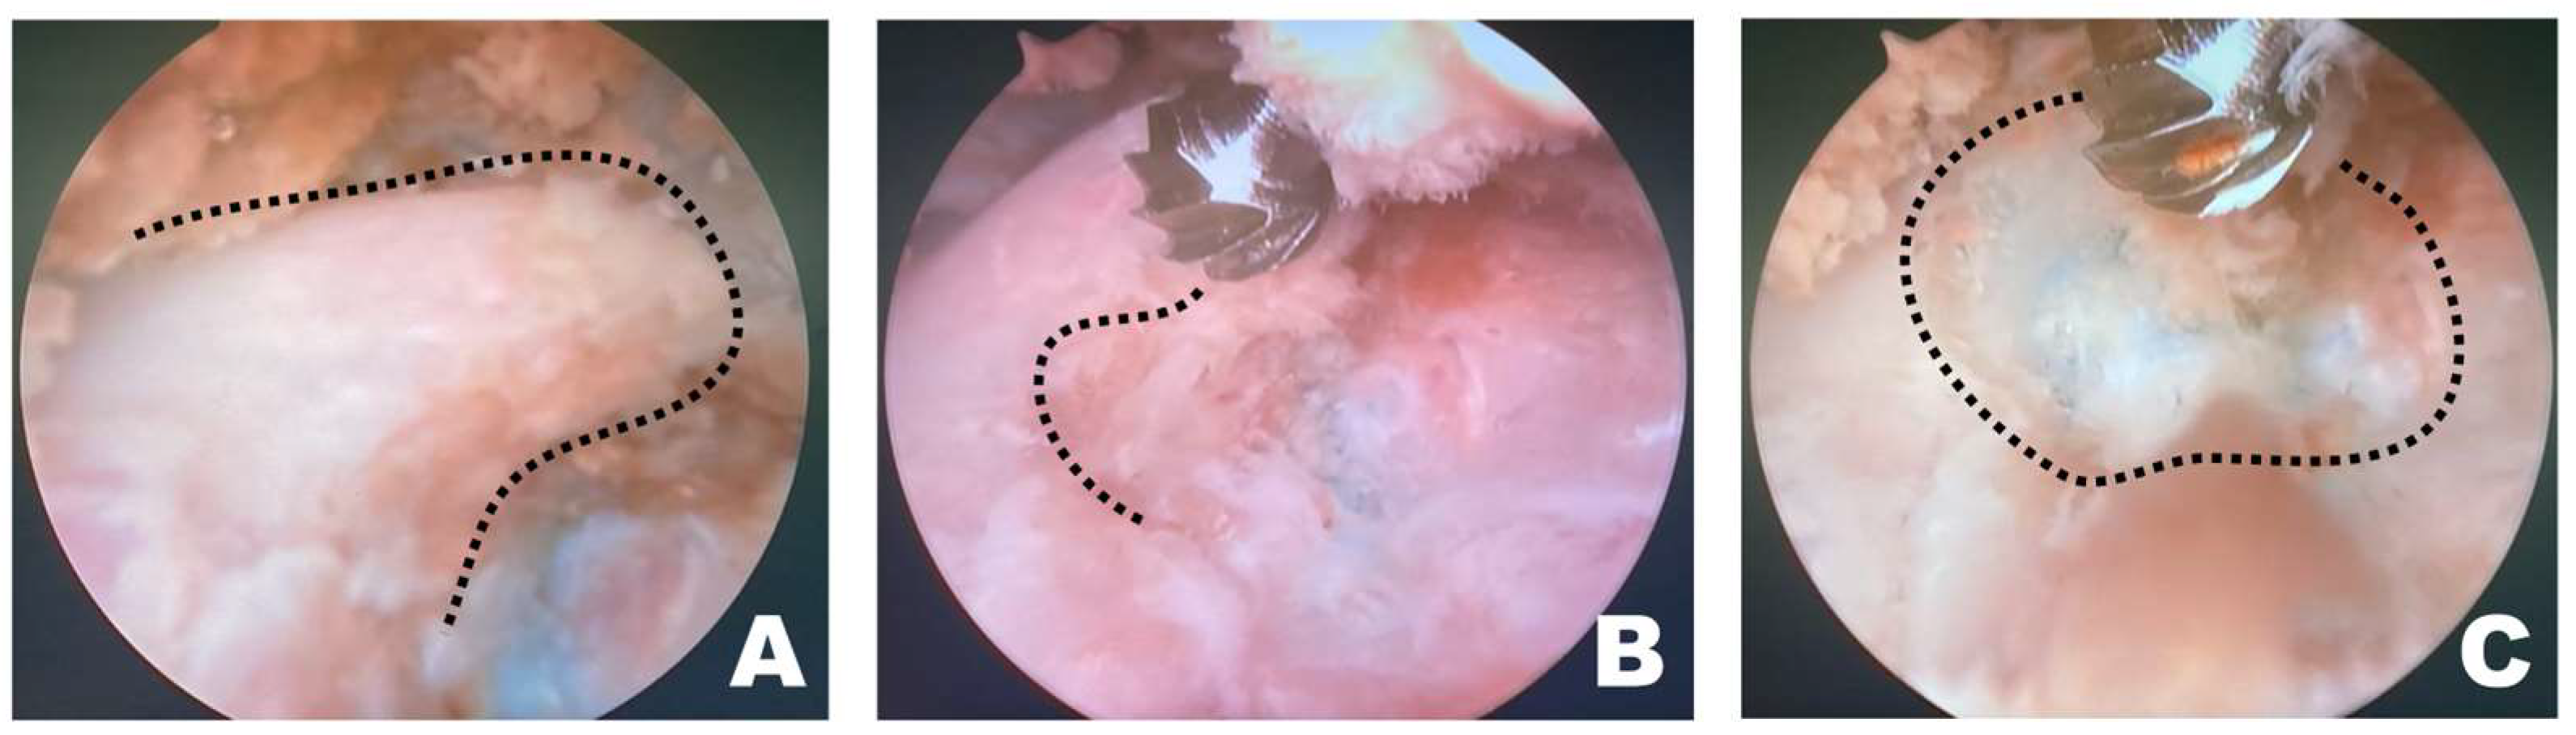

After verifying correct placement, the surgeon focused on the monitor connected to the scope (Figure 3A). If the working space was clearly visible through the scope, forceps and punches were used to remove the epaxial muscles attached to the accessory process or any surrounding tissue that hindered visualization. Following the excision of the larger epaxial muscles, smaller tissues that were difficult to remove with forceps and punches were cleared using RF tools suitable for the situation, creating a cleaner view of the working space (Figure 3B). The longissimus thoracis was incised using an appropriate RF tool to expose the accessory process (Figure 3C).

Figure 3.

Removal of soft tissue in the endoscopic view toward the left. (A) The surgeon performed the surgery while facing the monitor in front. The white arrow indicates the direction of the surgeon’s gaze during the surgery. (B) When radiofrequency (RF) tools were applied to the epaxial muscles in the left endoscopic view, tissue cauterization, vessel coagulation, and bubble formation were observed. (C) RF tools were used to dissect soft tissue attached to the accessory process, which became visible (red dotted line) after separation of the longissimus thoracis muscle.

Once a clear view of the working space for accessory process osteotomy was established (Figure 4A), burr osteotomy was performed to ensure that it was securely seated on the wider surface of the caudal aspect of the accessory process to prevent slipping (Figure 4B). Thus, the osteotomy site served as the surgical window (Figure 4C). If nerve exposure and potential nerve damage increased owing to insufficient burr osteotomy, an additional osteotomy was performed with a shaver. If precise soft tissue trimming was performed, FDADM-MB could be observed through the transforaminal site without osteotomy of the accessory process, alongside the epidural fat (Figure 4).

Figure 4.

Osteotomy of the accessory process in the endoscopic view toward the left. (A) The dashed line indicates the T12 accessory process. Clear and distinct observation was possible; the fluorescently dyed artificial disc material with methylene blue was observed at this time. (B) The dashed line marked the initiation point of osteotomy. Osteotomy was performed by securely placing the burr on the widest surface of the caudal aspect of the accessory process. (C) The dashed line indicates the surgical window. Additional osteotomy was extended along the dashed line.